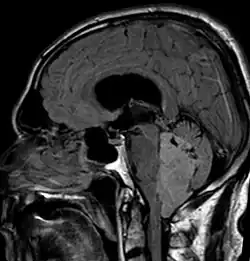

An ependymoma is a tumor that arises from the ependyma, a tissue of the central nervous system. Usually, in pediatric cases the location is intracranial, while in adults it is spinal. The common location of intracranial ependymomas is the floor of the fourth ventricle. Rarely, ependymomas can occur in the pelvic cavity.

Ependymomas make up about 5% of adult intracranial gliomas and up to 10% of childhood tumors of the central nervous system (CNS). Their occurrence seems to peak at age 5 years and then again at age 35. They develop from cells that line both the hollow cavities of the brain and the central canal containing the spinal cord, but they usually arise from the floor of the fourth ventricle, situated in the lower back portion of the brain, where they may produce headache, nausea and vomiting by obstructing the flow of cerebrospinal fluid. This obstruction may also cause hydrocephalus. They may also arise in the spinal cord, conus medullaris and supratentorial locations.[7] Other symptoms can include (but are not limited to): loss of appetite, difficulty sleeping, temporary inability to distinguish colors, uncontrollable twitching, seeing vertical or horizontal lines when in bright light, and temporary memory loss. It should be remembered that these symptoms also are prevalent in many other illnesses not associated with ependymoma.

Although some ependymomas are of a more anaplastic and malignant type, most of them are not anaplastic. Well-differentiated ependymomas are usually treated with surgery. For other ependymomas, total surgical removal is the preferred treatment in addition to radiation therapy. The malignant (anaplastic) varieties of this tumor, malignant ependymoma and the ependymoblastoma, are treated similarly to medulloblastoma but the prognosis is much less favorable. Malignant ependymomas may be treated with a combination of radiation therapy and chemotherapy. Ependymoblastomas, which occur in infants and children younger than 5 years of age, may spread through the cerebrospinal fluid and usually require radiation therapy. The subependymoma, a variant of the ependymoma, is apt to arise in the fourth ventricle but may occur in the septum pellucidum and the cervical spinal cord. It usually affects people over 40 years of age and more often affects men than women.[10]

Intracranial ependymomas, including supratentorial and posterior fossa, make up 90% of ependymomas in children. The supratentorial region is the upper brain region, or cerebrum, and contains the lateral and third ventricles. The posterior fossa, or infratentorial, is behind or below this region in the area of the brainstem and cerebellum and contains the fourth ventricle. A majority of intracranial pediatric ependymomas are in the posterior fossa.[15] Patients with intracranial ependymomas typically present with increased intracranial pressure that results in headaches, dizziness, nausea, and vomiting. The third location of ependymomas is within the central canal of the spinal cord. Spinal ependymomas comprise about 65% of adult ependymomas and most often occur in the lumbosacral region.[13] Patients with spinal ependymomas can present with back pain, numbness or weakness in the limbs, and urinary or bowel problems.